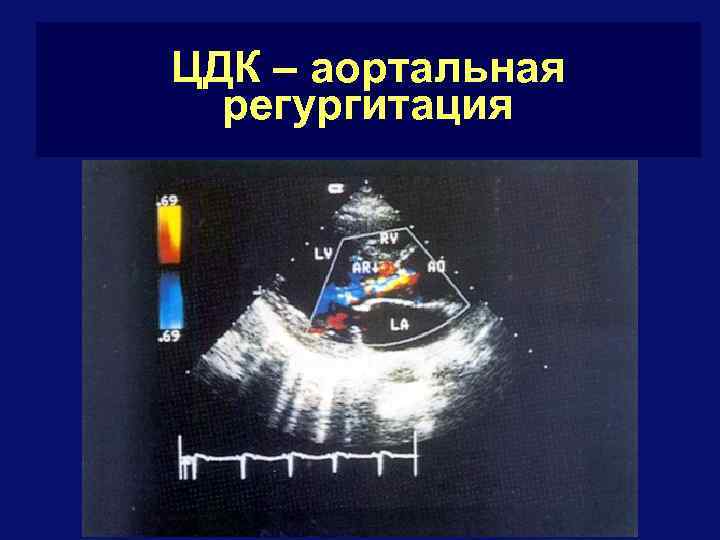

ЦДК – аортальная регургитация